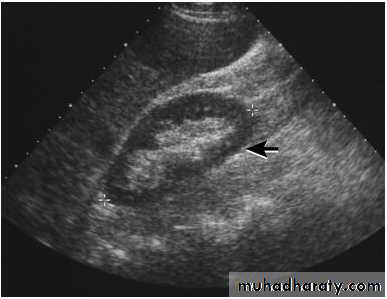

The kidney is bean shaped and has bright central echoes because of the fat surrounding the collecting system.

Normal renal ultrasound.

A longitudinal view of the right kidney was obtained by passing the sound beam through the right lobe of the liver. The kidney is seen behind this, outlined by the markers. The central bright echoes in the kidney are due to fat around the collecting system.